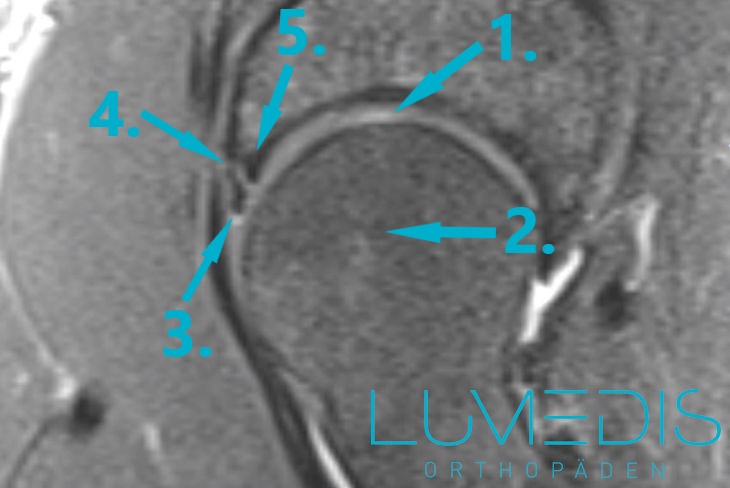

Mittels eines MRTs der Hüftekann man eine Labrumläsion beweisen oder ausschließen. Es sollte also immer dann durchgeführt werden, wenn man diese Art von Verletzung vermutet, ein Beweis aber noch aussteht. Nach stärkeren Verletzungen sollte man immer ein MRT der Hüfte durchführen, die zeigen soll, ob auch das Labrum verletzt ist.